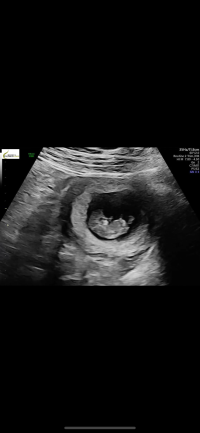

9+0, 178 bpm og 2,3cm lang. Perfekt liten miniatyrbaby som danset for oss på skjermen!